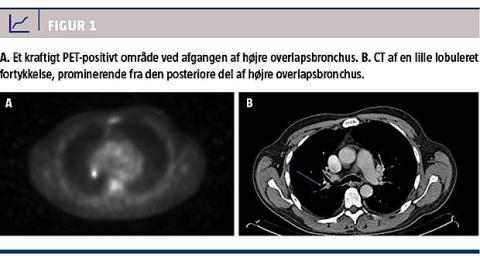

En 60-årig mand blev indlagt med henblik på operation for nasalpolypper. Han havde ingen symptomer fra lunger eller luftveje trods rygning svarende til 50 pakkeår. Røntgenundersøgelse af thorax og lungefunktionsmåling viste normale forhold. I forbindelse med et videnskabeligt projekt blev der med patientens accept foretaget bronkoskopi. I højre overlaps andet segment fandt man en lille tumor af typen planocellulært karcinom. PET-CT viste et 0,8 cm stort metabolisk aktivt område, som strakte sig ind i lumen med klassifikation T1aN0M0 (Figur 1). Præoperativ rebronkoskopi afslørede imidlertid, at tumoren faktisk involverede både første og andet segment samt hovedbronchus, altså T2a i stedet for T1a. Konsekvensen var, at man i stedet for en torakoskopisk lobektomi valgte åben muskelbesparende torakotomi med lobektomi og sleeve resection, hvor lappen blev fjernet sammen med den involverede del af højre hovedbronchus. Efterfølgende blev der foretaget en anastomose mellem højre hovedbronchus og højre intermediærbronchus. Der blev ligeledes foretaget systematisk lymfeknudedissektion uden fund af lymfeknudemetastaser. Den endelige TNM-klassifikation var således T2aN0M0, stadie Ib. Patienten havde efter to år ikke fået recidiv, men en benign stenose krævede gentagne ballondilatationer.